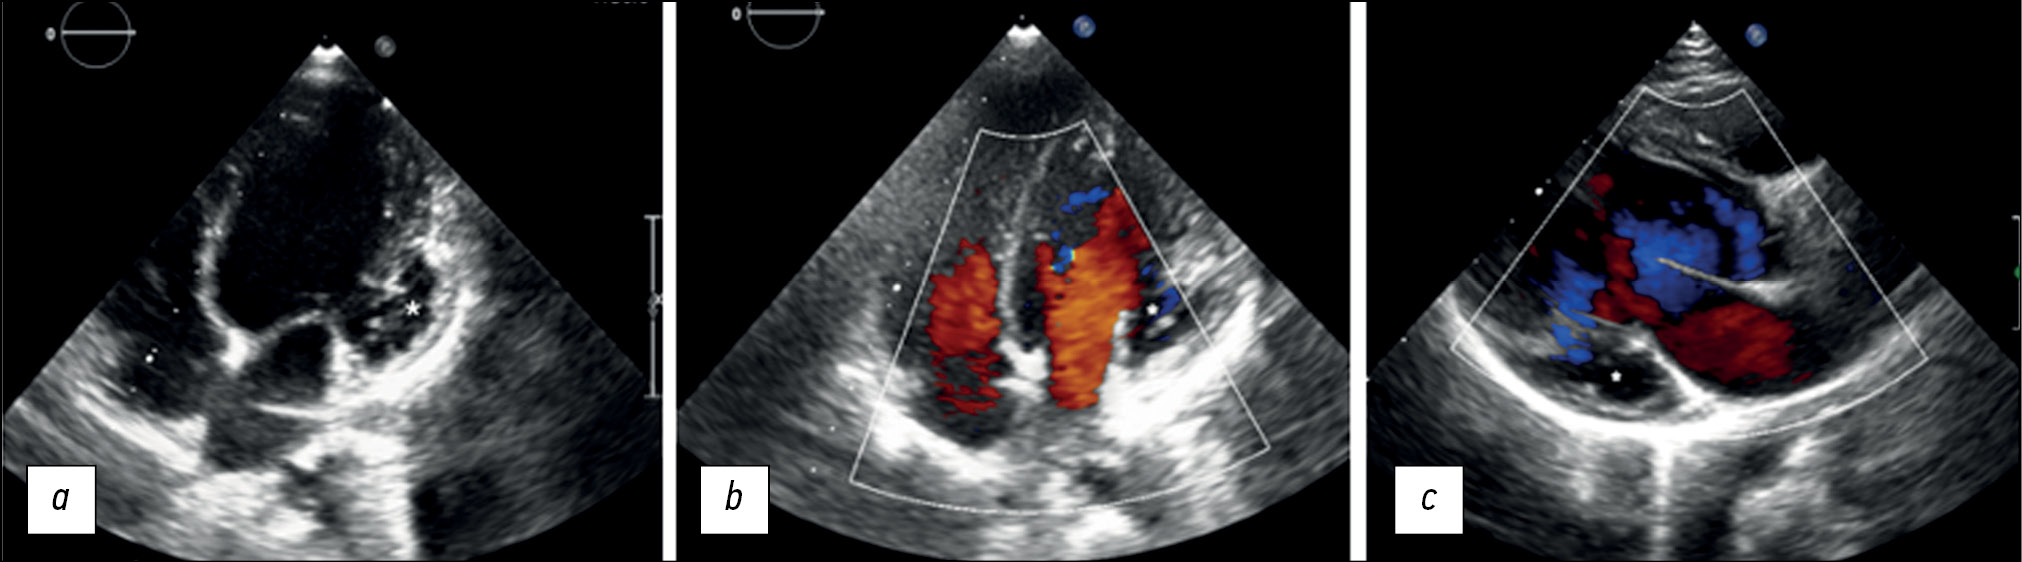

Left ventricular noncompaction with ventricular aneurysm in a 6-year-old patient

Abstract

Ventricular noncompaction is a rare type of cardiomyopathy often associated with a ventricular aneurysm. We present a clinical case of a 6-year-old female who arrived at our clinic complaining of physical exertion. Echocardiography revealed prominent trabeculations in the left ventricular wall and a lateral-basal part bulging out, indicating noncompaction of the left ventricular myocardium with an aneurysm. With a noncompacted-to-compacted myocardium ratio of 2.6, magnetic resonance imaging revealed the presence of noncompacted myocardium. It also revealed impaired left ventricular systolic function and a left ventricular aneurysm with myocardial scarring. Coronary angiography ruled out coronary artery disease. Therefore, myocardial scarring was caused by noncompacted myocardium microcirculatory disorder.

625-632